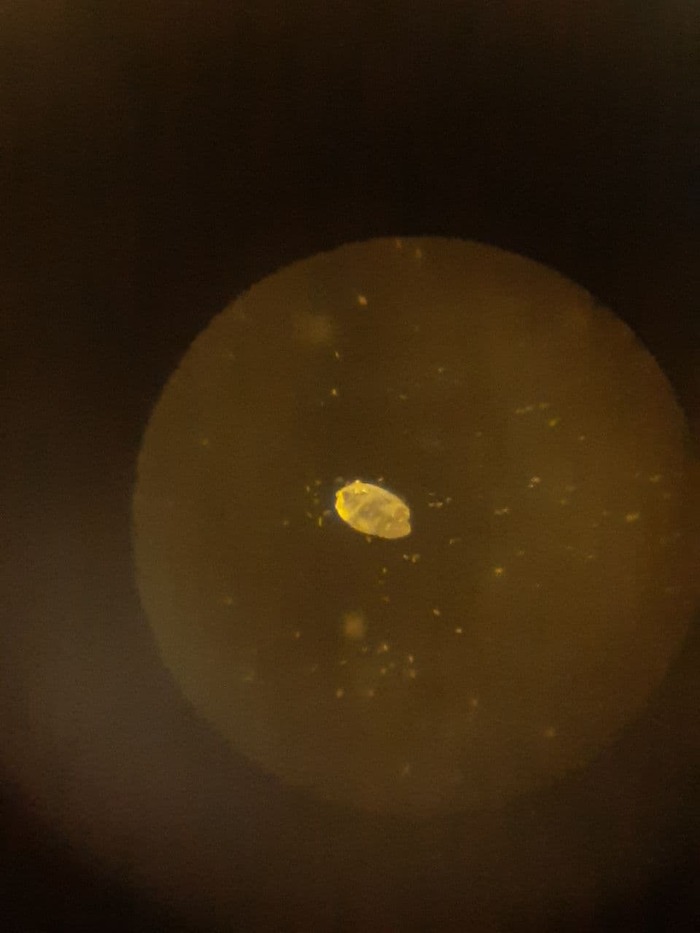

Купил недавно простой детский микроскоп и вот что обнаружилось...

Увеличенное фото и немного повернуто:

Я как писал ранее вот что увидел в микроскопе, конечно покажу данные фото на следующем приеме, но что вы думаете по этому поводу? Наверняка есть специалисты, которые могут помочь определить что это за неведомый зверь? Может новая форма жизни?